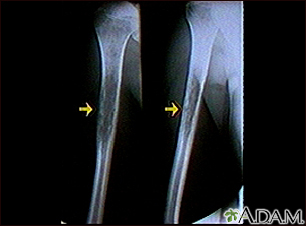

Ewing sarcoma - x-ray